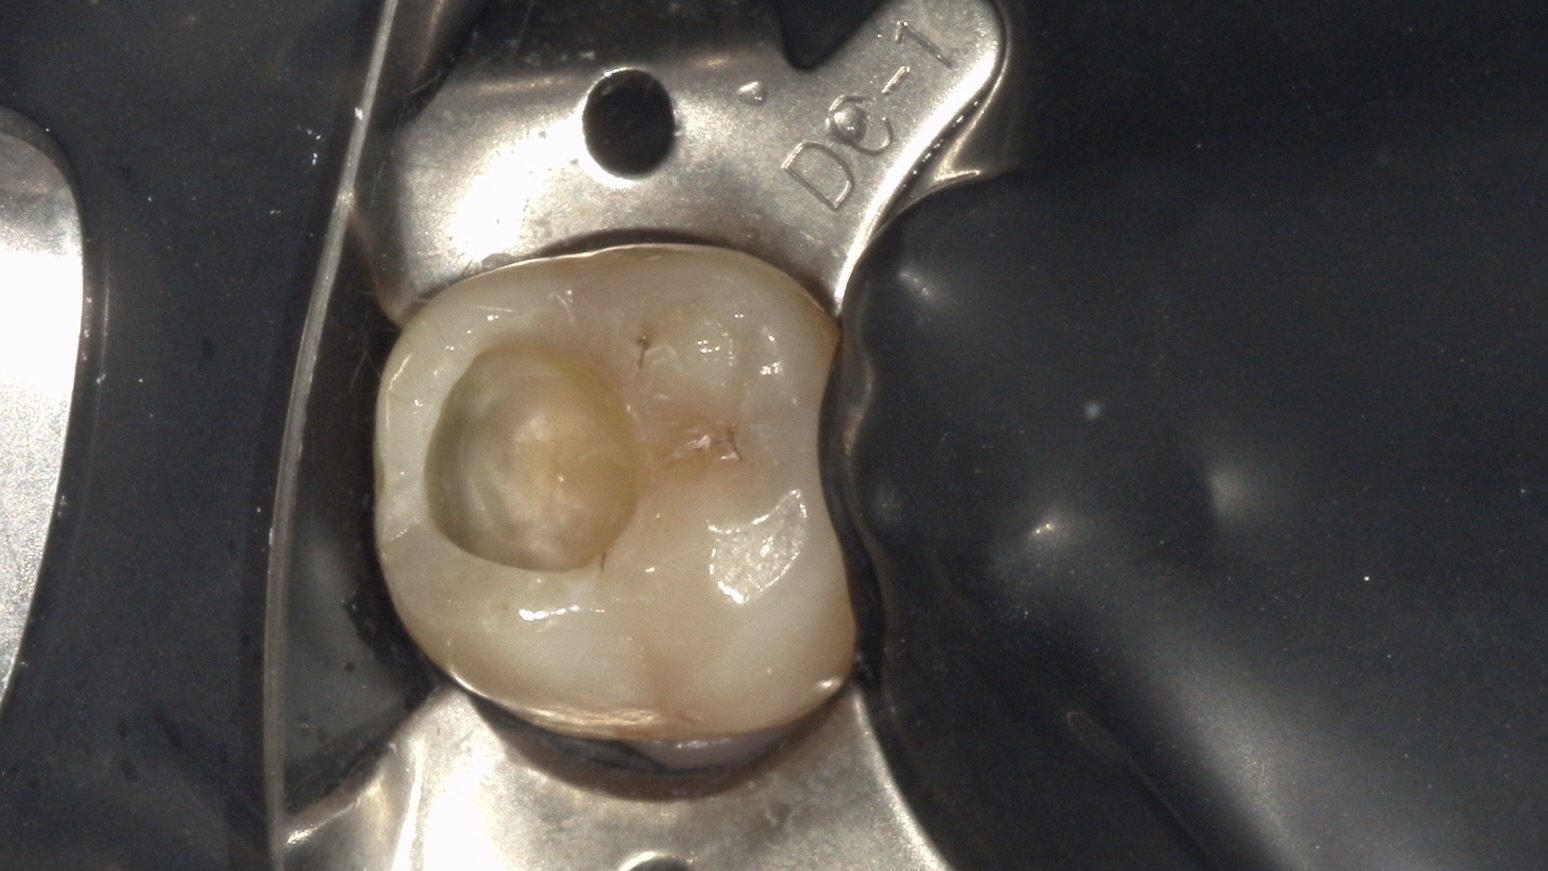

むし歯を除去し、ラバーダム防湿

ダイレクトボンディング後